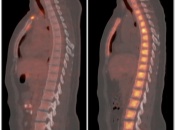

Normal Skeletal Uptake

Mild to moderate FDG uptake can be normally seen within red marrow, most commonly affecting the vertebral bodies, sternum, pelvis, and proximal long bones (it is not unusual to see fairly prominent uptake within the proximal half of the femurs). This red marrow uptake can be quite heterogeneous at times, yet still normal.

Diffuse Skeletal Uptake:

Intense and diffuse reactive marrow uptake is frequently seen as the result of chemotherapy and/or colony stimulating factors (discussed in detail, here).

If rather diffuse and intense uptake is noted without a history of recent chemotherapy or colony stimulating factors, be suspicious of infiltrating disease such as lymphoma.